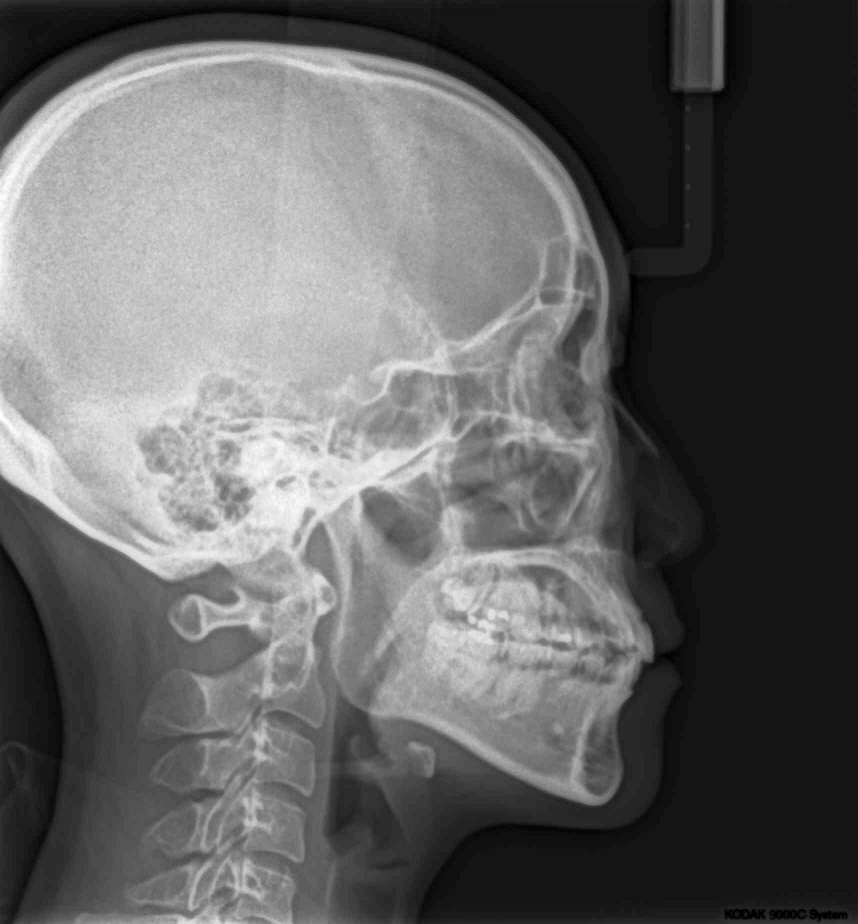

우선 저는 성인이구요(20대 후반) 사진에서 보이다시피 아래쪽에 유치가 두개 있는 상태입니다. 이걸 임플란트를 할지 교정으로 이를 밀어버릴지 고민이예요. 임플란트로만 처리한다면 더 오래 유치를 가지고 있어도 ...